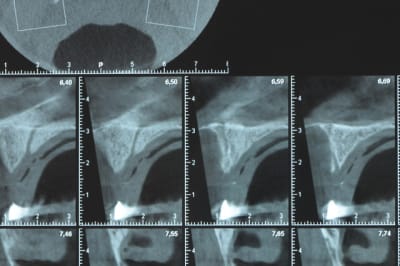

Une petite étude de ton cas D57

Sous réserves bien sur de voir l’animal en vrai

Les zones exploitables radiologiquement parlant:

Coupes implant

2,3 40100

4,96 35130 avec sinus lift mais difficile

5,25 35150

6,02 35130

6,78 35115 après réduction de hauteur de crête

7,26 35115 après réduction de hauteur de crête

8,51 35150

10,43 40115 ou 50115

11,10 40115

Ce qui nous fait 9 implants possible évidement avec un comblement de sinus on augmenterait encore les zones implantable mais ce n’est pas le but recherché, avec 8 (4+4) il doit être possible de faire une belle barre support de complet